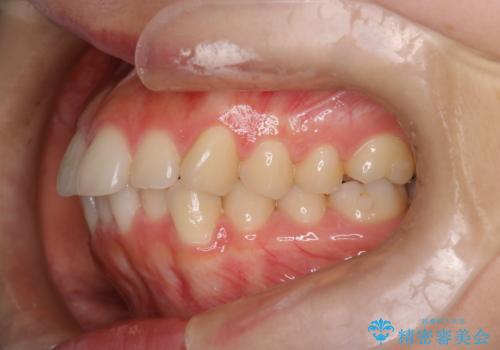

下顎前歯の叢生を短期間で改善

- 患者様は、下顎前歯のガタガタ(叢生)の改善を希望して来院されました。診断の結果、非抜歯で治療可能であると判断し、透明で目立たないインビザラインを使用する矯正治療計画を立案しました。短期間での治療を希望されていたため、IPR(歯間削合)を併用してスペースを確保しながら、効率的に歯を並べることを目指しました。

治療では、インビザラインを用いて計画的に歯を移動させ、短期間での歯列改善を実現しました。IPRを行うことで、抜歯をせずに必要なスペースを確保し、歯列全体を整えました。治療中は、装置の適切な装着時間を守ることが重要であり、患者様にも継続的な協力をお願いしました。また、歯肉や歯根への負担を最小限に抑えるため、歯の移動を慎重に管理しました。結果として、短期間で下顎前歯の叢生を改善し、自然な見た目と機能性を兼ね備えた歯列を実現できました。